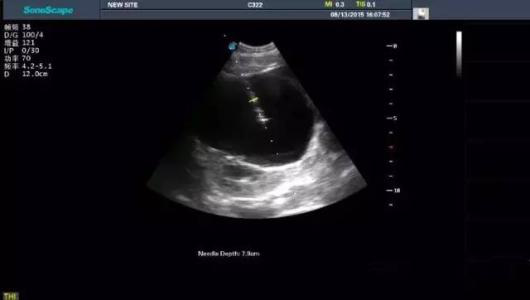

程印蓉主任通过详实的病例分析,重点展示了乳腺超声造影技术的临床应用成果:

近期通过该技术诊断两例乳腺癌(BI-RADS 5类)并协助患者及时入院手术,病理结果与术前诊断高度一致;另有一例在外院初判为恶性肿瘤(4b类)的疑难病例,经我院超声造影动态评估降类至3类,最终手术证实为纤维腺瘤伴钙化及骨化。

这些典型案例充分验证了超声造影在乳腺结节良恶性鉴别中的优势。

基于近年的临床应用数据,程主任系统阐释了超声造影在提升诊断准确率、优化临床决策中的重要作用。通过多模态超声评估,不仅能清晰显示病灶微循环特征,更能动态观察造影剂灌注模式,为乳腺结节分类提供可靠依据。